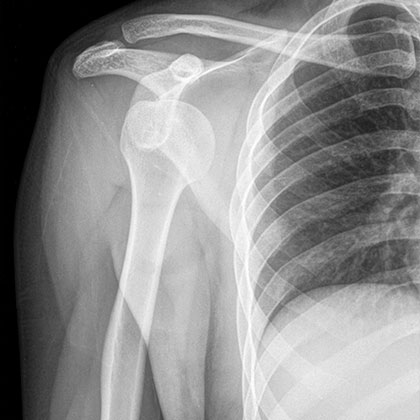

석회성건염은 어깨의 힘줄이 손상되거나 파열되어 혈액순환이 제대로 이루어지지 않을 경우 힘줄 주변에 칼슘이 쌓여 석회가 침착되는데 비교적 젊은 연령층에서 잘 발생하는 질환이며 특별한 이유 없이 갑자기 극심한 통증이 발생하는 것이 특징입니다.

석회성건염은 X-ray검사로 쉽게 진단이 가능합니다. 석회의 크기와 위치 등을 X-ray상 확인할 수 있지만 어깨 힘줄 상태를 정확히 알기 위해서는 초음파 검사와 MRI검사가 필요한 경우가 있습니다